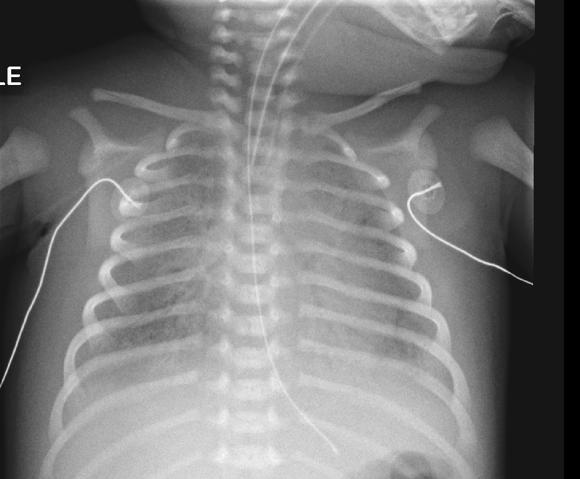

After ensuring that the airway is patent and that breathing is managed with high flow oxygen, intravascular access should be gained. This may be achieved with a large bore cannula intravenously or by inserting an intraosseous needle. Administer a 10ml/kg bolus of isotonic fluid (0.9% saline or a balanced solution such as Hartmann’s or Plasmalyte-148).

Self-inflating bags are available in a number of sizes depending on the manufacturer (250ml, 400500ml, and 900ml-1.6L). The medium sized 450-500ml bags are suitable for use in paediatric patients; although larger bags (900ml-1.5L) can be used if a smaller bag is not available. The pressure exerted on the bag should only be sufficient to support the tidal volume of the child and see chest rise. The

250ml bag is intended for use in neonates only. The bags used in infants and smaller children should have a “pop-off” pressure limiting valve which alerts the rescuer that excessive pressure is being delivered. The pop-off pressure is set by the manufacturers but is generally around 40 cmH2O. If required the valve can be over-ridden but then excessive pressure may be delivered increasing the risk of pneumothorax.